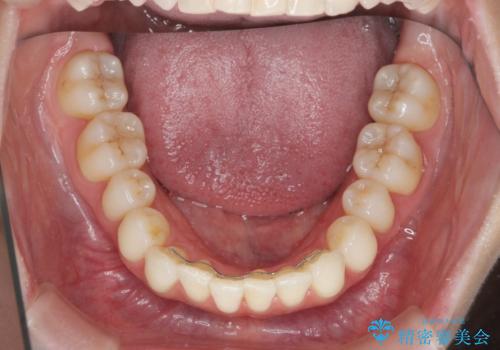

昔ワイヤー矯正をして後戻りした 軽度のがたつき モニター矯正

- 矯正治療後の後戻りを主訴に来院。

特に下の前歯のがたつきを気にされていました。

マウスピース矯正で再矯正を行いました。

再度の後戻りを防ぐため、下顎前歯の裏にはワイヤーを貼る保定を行っています。